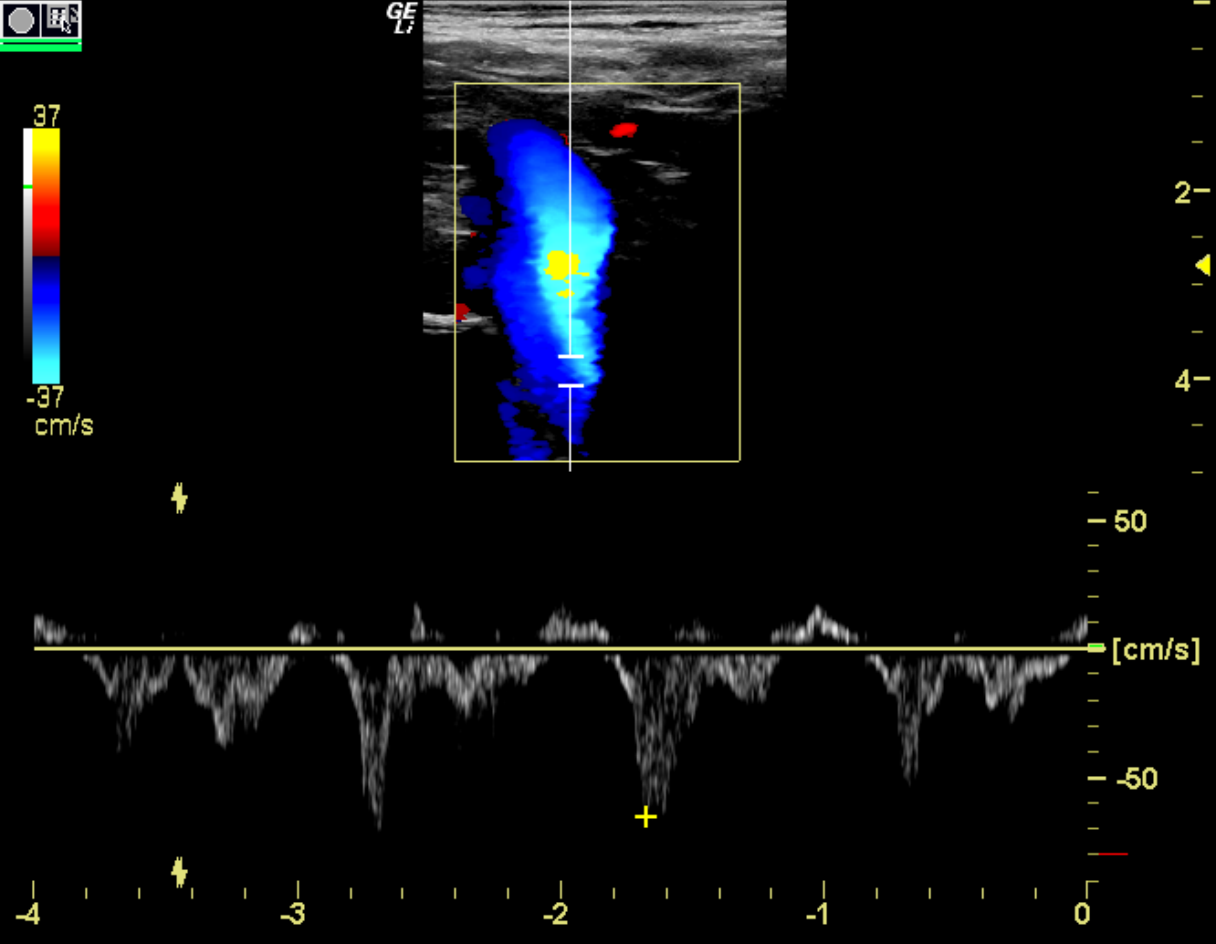

ultrasound image of the brachiocephalic vein